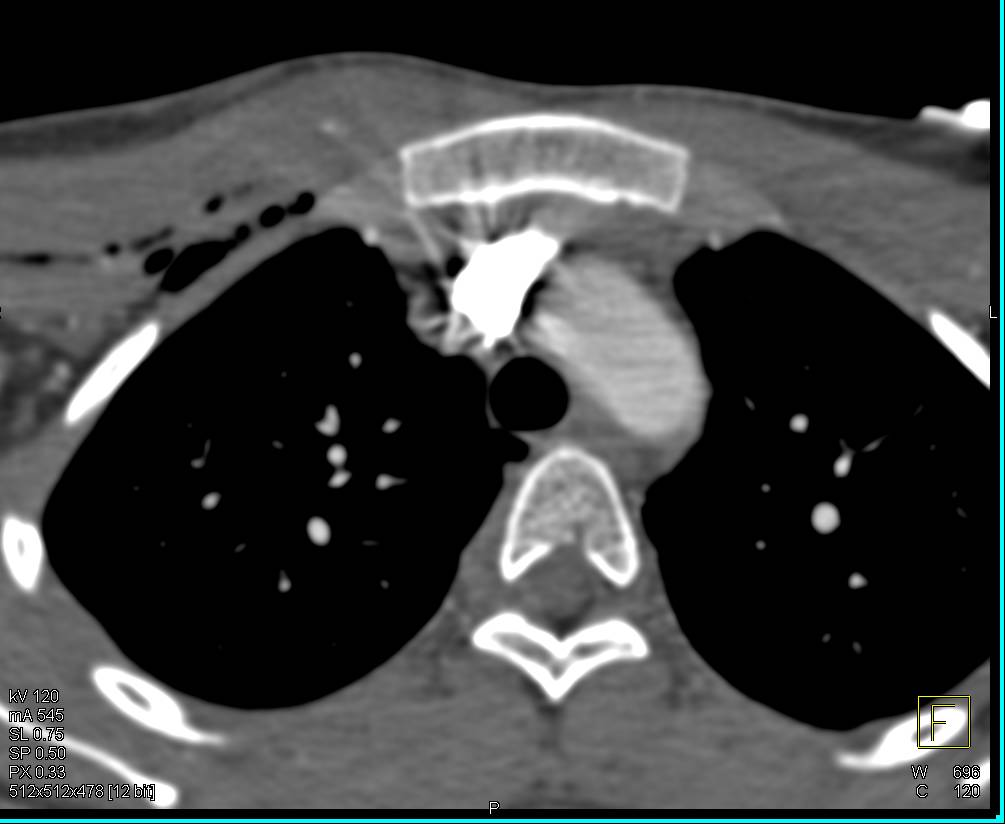

Aortic Valve Calcification with Aortic Stenosis and Dilated Ascending Aorta. Coronary Artery Disease Also Seen